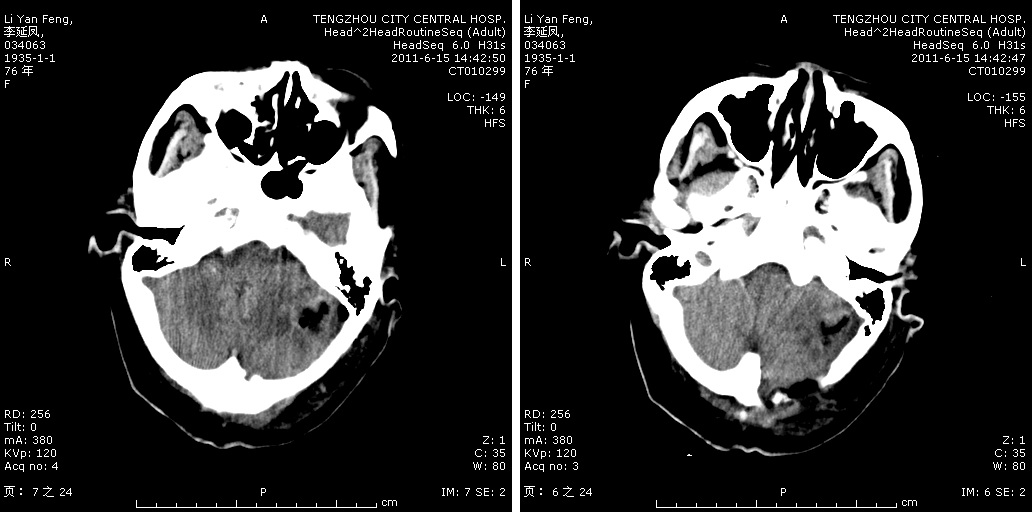

三叉神经微血管减压手术切口

术中显微镜镜下神经显露